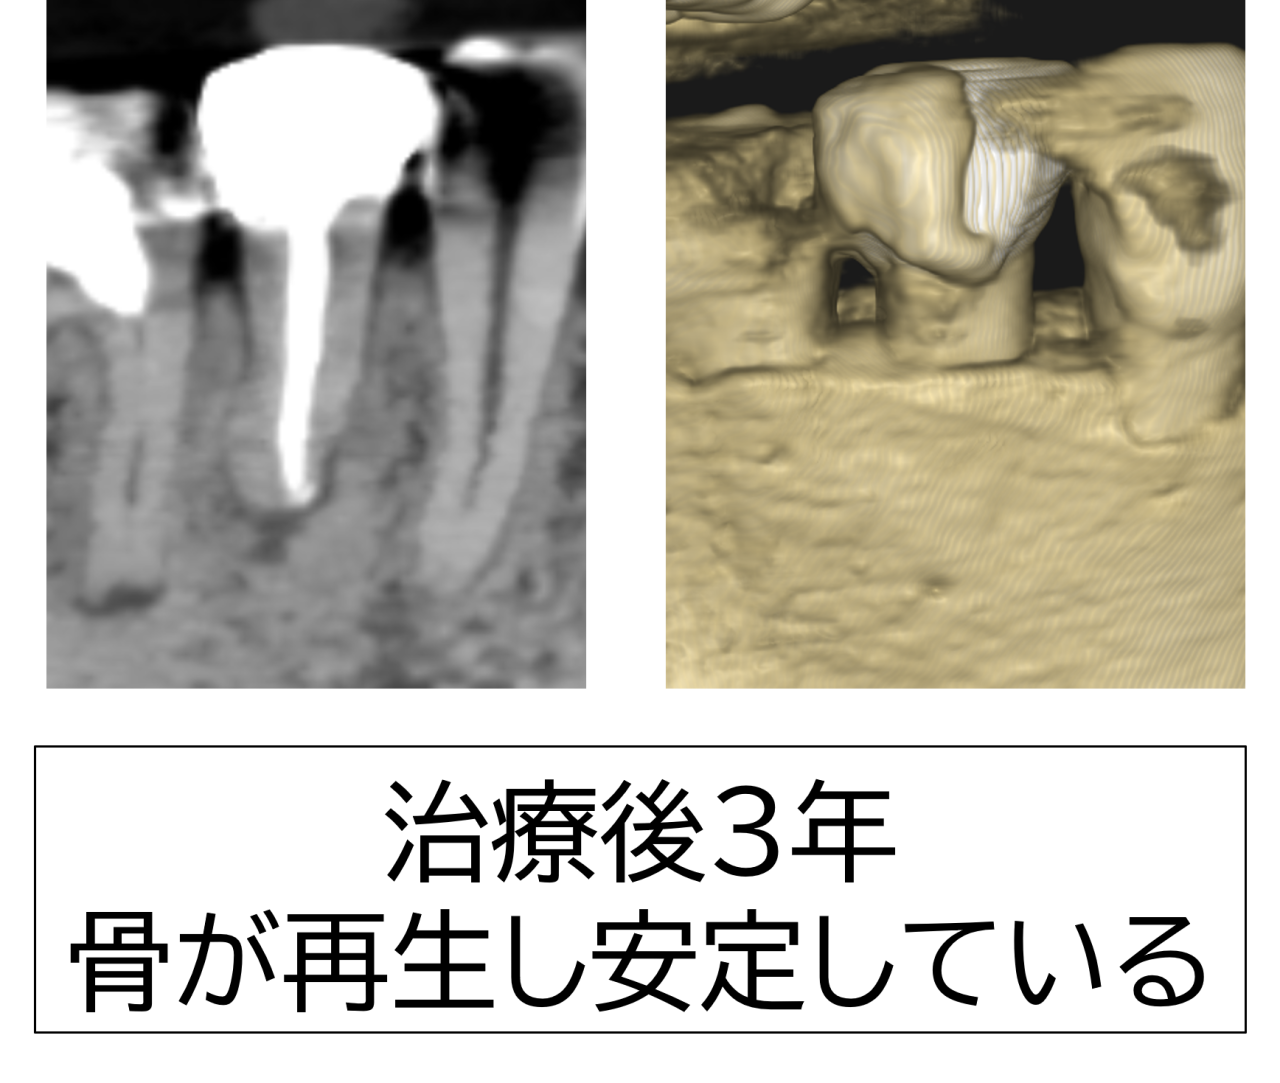

3年後のレントゲンでは骨がほぼ完全に再生していました。これからも長期的に安定した状態が保てるように経過観察していきます。患者様は非常に喜ばれました。本当に良かったです。

Q. 骨は本当に再生しますか?

A. 感染源を取り除けば、体の自然な治癒力で少しずつ骨が再生してくることが多いです。今回の症例でもレントゲンで再生を確認できました。